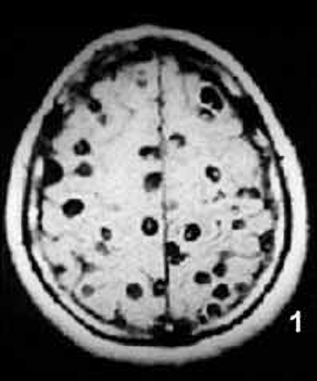

病院では頭部MRIと全身CTスキャンが行われたが、その検査結果は専門家さえも驚く衝撃的なものだった。

それもそのはず、女性の全身はすでに無数の寄生虫に侵されており、大脳や顔面の筋肉にさえも感染が見られるひどい

有様だったからだ。

医師の話では、女性の体内の寄生虫の一部はすでに死に、石灰化しており、全身の痛み以外に眼球突出や

網膜出血といった症状も見られたとのこと。治療はすぐに行われたものの、一部の寄生虫は体外に排出されず、

女性には後遺症が現れる可能性も否めないという。